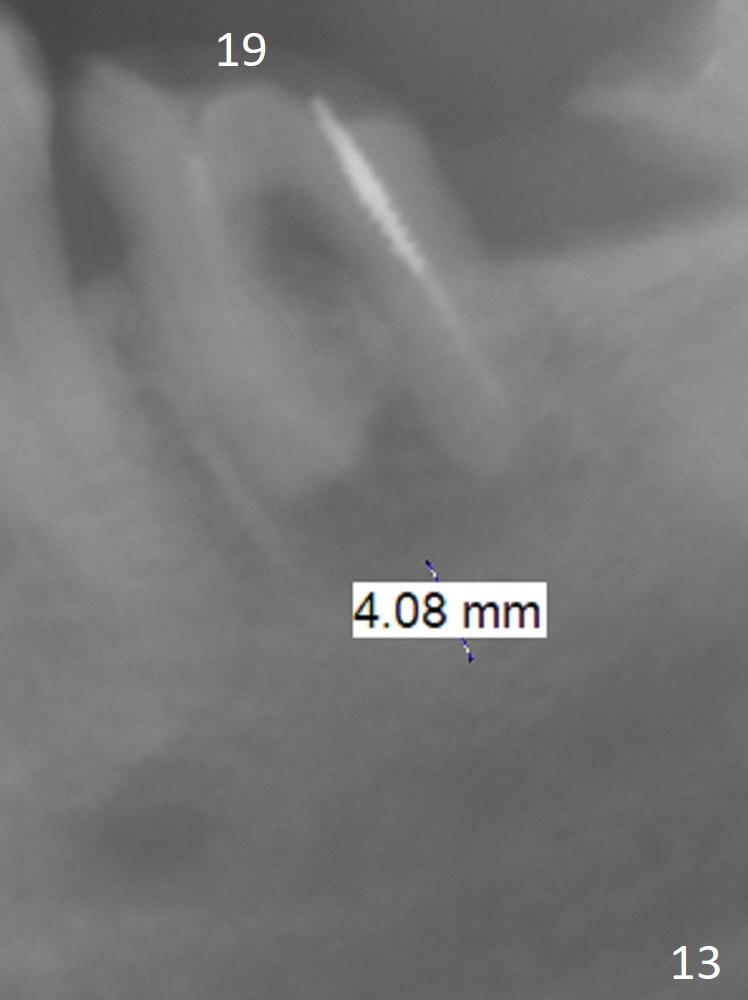

A 54-year-old man is 5 years post liver cancer surgery. After his platelet count returns normal, he wants to take care of his teeth. Most of his molars (#14, 19, 30,31) need extraction and implant placement (Fig.1-4). Although the 2nd premolars on the right are missing (Fig.1,3,4), it seems appropriate to establish 2 molar occlusion on the right (Fig.5,7,8) and 1 on the left (Fig.6,7 (because of #15 supraeruption (Fig.2 arrow))) . Since the residual roots in the lower right quadrant are irritating, implant placement will be done first (Fig.11, Clindamycin), followed by #2,3 (Fig.10) and 14(Fig.12 IBS) and 19 (Fig.12). Use IS drills and 4 and 5 mm stoppers to start osteotomy at #30 and 31, respectively.